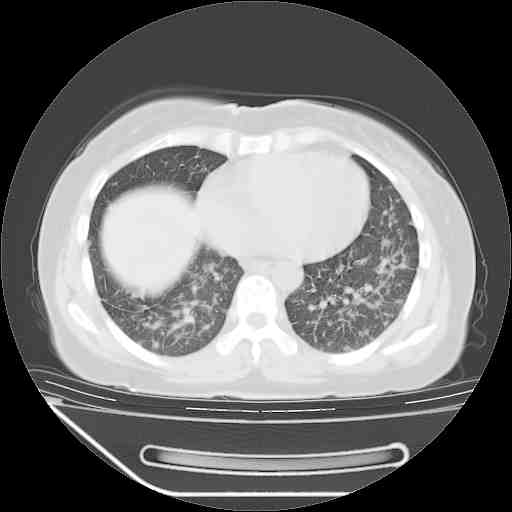

下面是今天刚刚做的,在上海治疗,吃了家属也说不清的一种药,一个月1万左右,

考虑  腺癌肺内转移,治疗较前病灶缩小、减少

支持肺癌并肺内淋巴管转移,

支持肺癌并肺内淋巴管炎,  原发灶小了,但转移较前片明显了.

支持右肺下叶周围型肺癌并肺内淋巴管炎,  原发灶小了,但转移较前片明显了.。

标准的细支气管肺泡癌呀!治疗后病情有所控制,也没治愈的迹象!

支持右肺下叶周围型肺癌并肺内淋巴管炎;病灶有所控制。